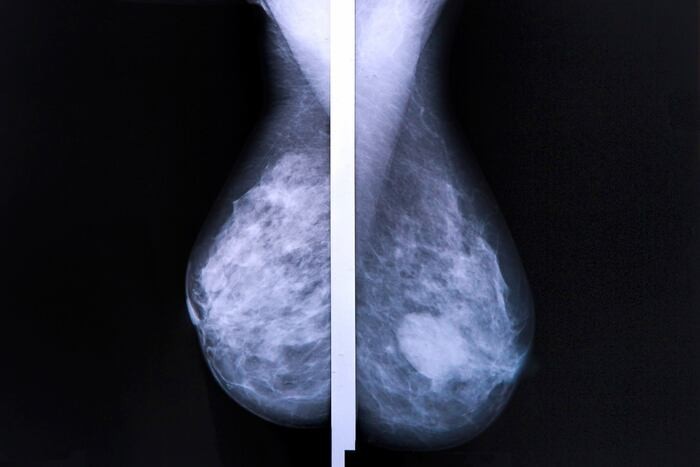

Diagnostikimi i kancerit të gjirit te gratë nën moshën 40 vjeç është më i vështirë, sepse indi i gjirit te to zakonisht është më i dendur se te gratë më të moshuara. Deri në momentin kur një nodus në gji mund të preket me dorë, kanceri mund të ketë arritur tashmë një fazë të avancuar.

Në përgjithësi, mamografitë e rregullta nuk rekomandohen për gratë nën moshën 40 vjeç, pjesërisht sepse indi i gjirit është më i dendur, gjë që e bën mamografinë më pak efektive. Shoqata Amerikane për Luftën kundër Kancerit rekomandon që gratë e moshës 40 deri në 44 vjeç të kenë mundësinë të vendosin vetë nëse duan të fillojnë skriningun vjetor me mamografi. Gratë nga 45 deri në 54 vjeç duhet të bëjnë mamografi çdo vit, ndërsa gratë 55 vjeç e lart duhet të vazhdojnë me mamografi çdo 1 deri në 2 vjet.

Shumica e ekspertëve mendojnë se rreziku i ulët në moshë të re nuk e justifikon ekspozimin ndaj rrezatimit, as kostot e mamografisë. Megjithatë, mamografia mund t’u rekomandohet grave më të reja që kanë histori familjare të kancerit të gjirit ose faktorë të tjerë rreziku.

Bisedoni me mjekun tuaj për kohën kur duhet të filloni mamografitë. Te gratë e reja, mamografia digjitale mund të jetë një alternativë ndaj mamografisë standarde, pasi zbulon më mirë parregullsitë në indin e dendur të gjirit.